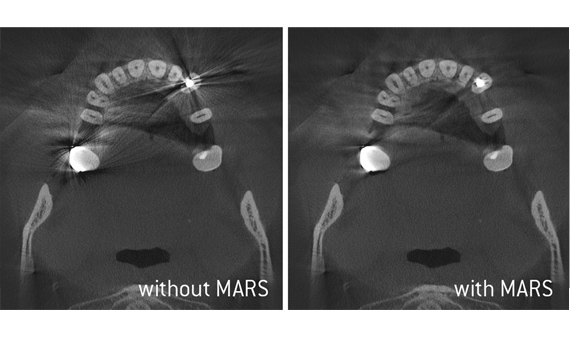

Efficient diagnostics thanks to exceptional image quality

Following the ALARA principle, our Axeos and Orthophos devices provide you the image quality you need for optimal diagnostic support at the lowest possible dose.